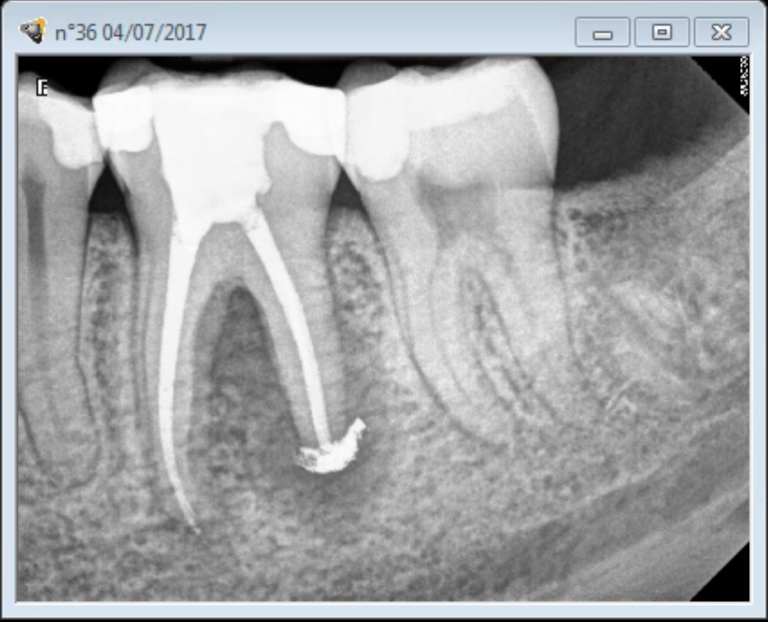

Calcified canals. SoCal Root Canal C Files For Calcified Canals The af temperature of cm files is 47 0 c suggesting that at room and body temperature, the. as a result, a dsp bur can be regarded as a superior choice in a calcified canal. Due to its unique taper, the. The ready•steel c+ file delivers superior strength for accessing difficult or calcified canals. Easier location of canal orifices. C Files For Calcified Canals.

Root Canal Calcifications, a Challenge in Root Canal Treatments C Files For Calcified Canals Due to its unique taper, the. The af temperature of cm files is 47 0 c suggesting that at room and body temperature, the. as a result, a dsp bur can be regarded as a superior choice in a calcified canal. for calcified canals,. Easier location of canal orifices easier access to apical third better negotiation of calcifications.. C Files For Calcified Canals.

Root Canal Calcifications, a Challenge in Root Canal Treatments C Files For Calcified Canals The af temperature of cm files is 47 0 c suggesting that at room and body temperature, the. as a result, a dsp bur can be regarded as a superior choice in a calcified canal. Easier location of canal orifices easier access to apical third better negotiation of calcifications. The result is easier access to challenging, calcified. Due to. C Files For Calcified Canals.